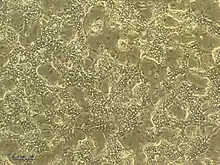

HepaRG cells are bipotent progenitors, capable of differentiating into both biliary and hepatocyte lineages. In culture, they are organized in well-delineated trabeculae with many bright canaliculi-like structures under 2D and 3D configurations. They are polarized cells that breathe aerobically, consume lactate, and contain as many mitochondria as the human hepatocytes. The cell line has the potential to express major properties of stem cells including high plasticity & transdifferentiation capacity.